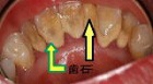

⑤歯肉が赤く腫れている